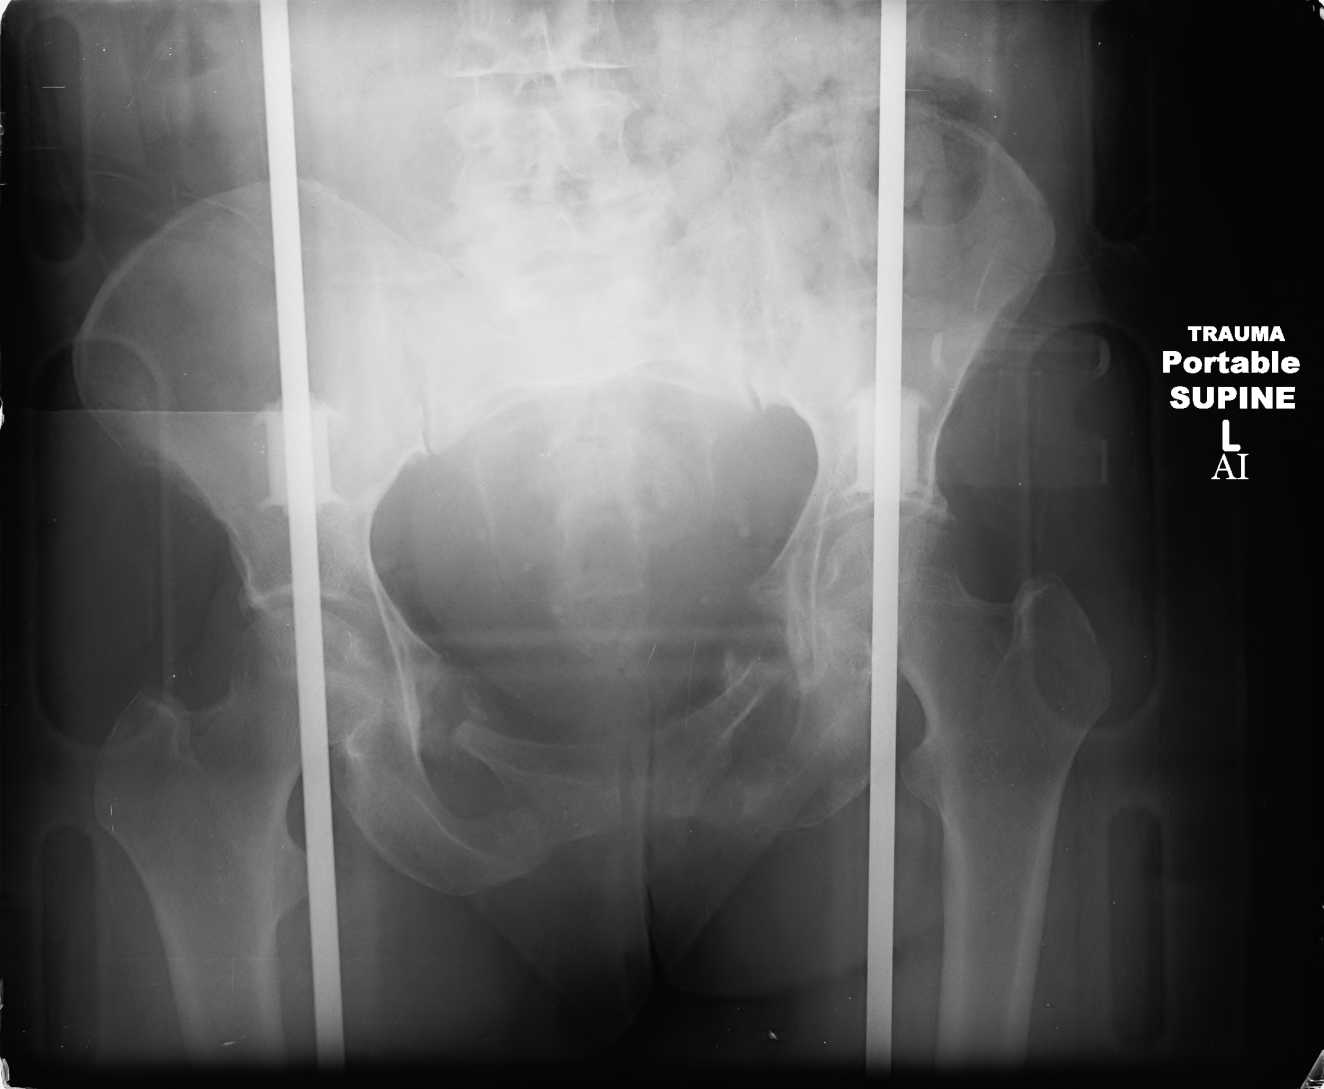

Here are a recent patient’s example slides...

54 yo Female Fell c/o Pain

Initial Films

?Instability on Exam - Limited by Pain

NonOp Initial Mgmt

3 Months After Fall

Continued Pain & Immobility

(+) Instability to Compressive Manual Exam

Pelvic CT Scan - 3 Months After Fall

Sacral Injuries

Ramus Fractures